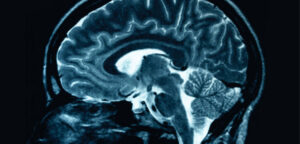

Una nuova ricerca trova come viene attivata una fondamentale e complessa proteina che svolge un ruolo chiave nella regolazione della...